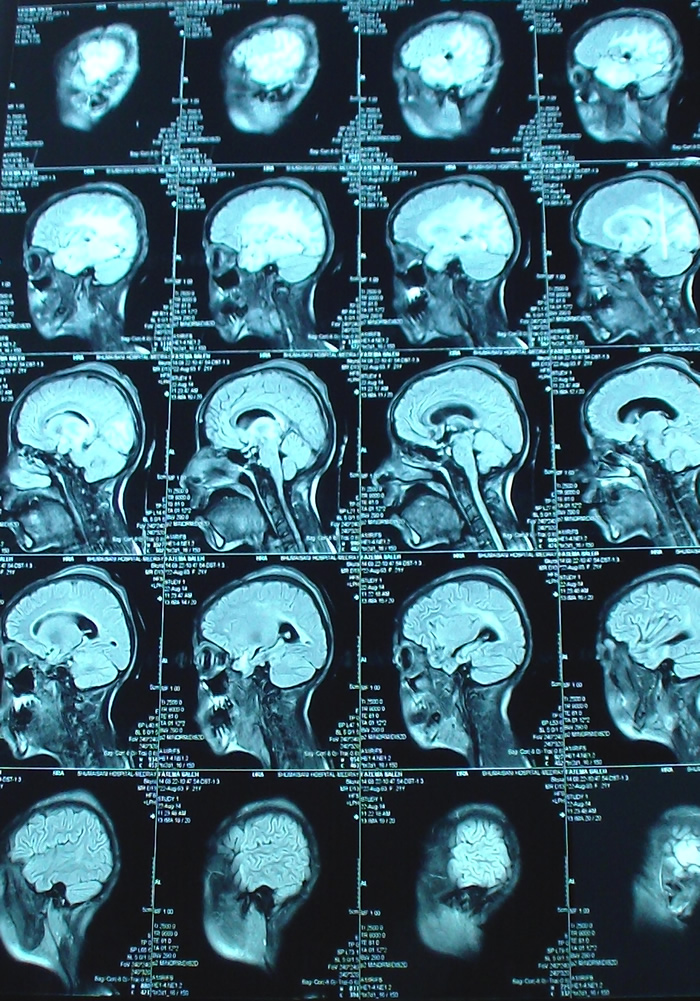

21-AUGUST-2014  FATMEH SALEH AL-DROOBI  20 YEARS RECURRENCE OF HIGHLY MALIGNANT GLIOMA RIGHT CONVEXITY.

Sagittal TW1  done the next postoperative day. Notice the radical resection, in comparison to the MRI done during surgery.